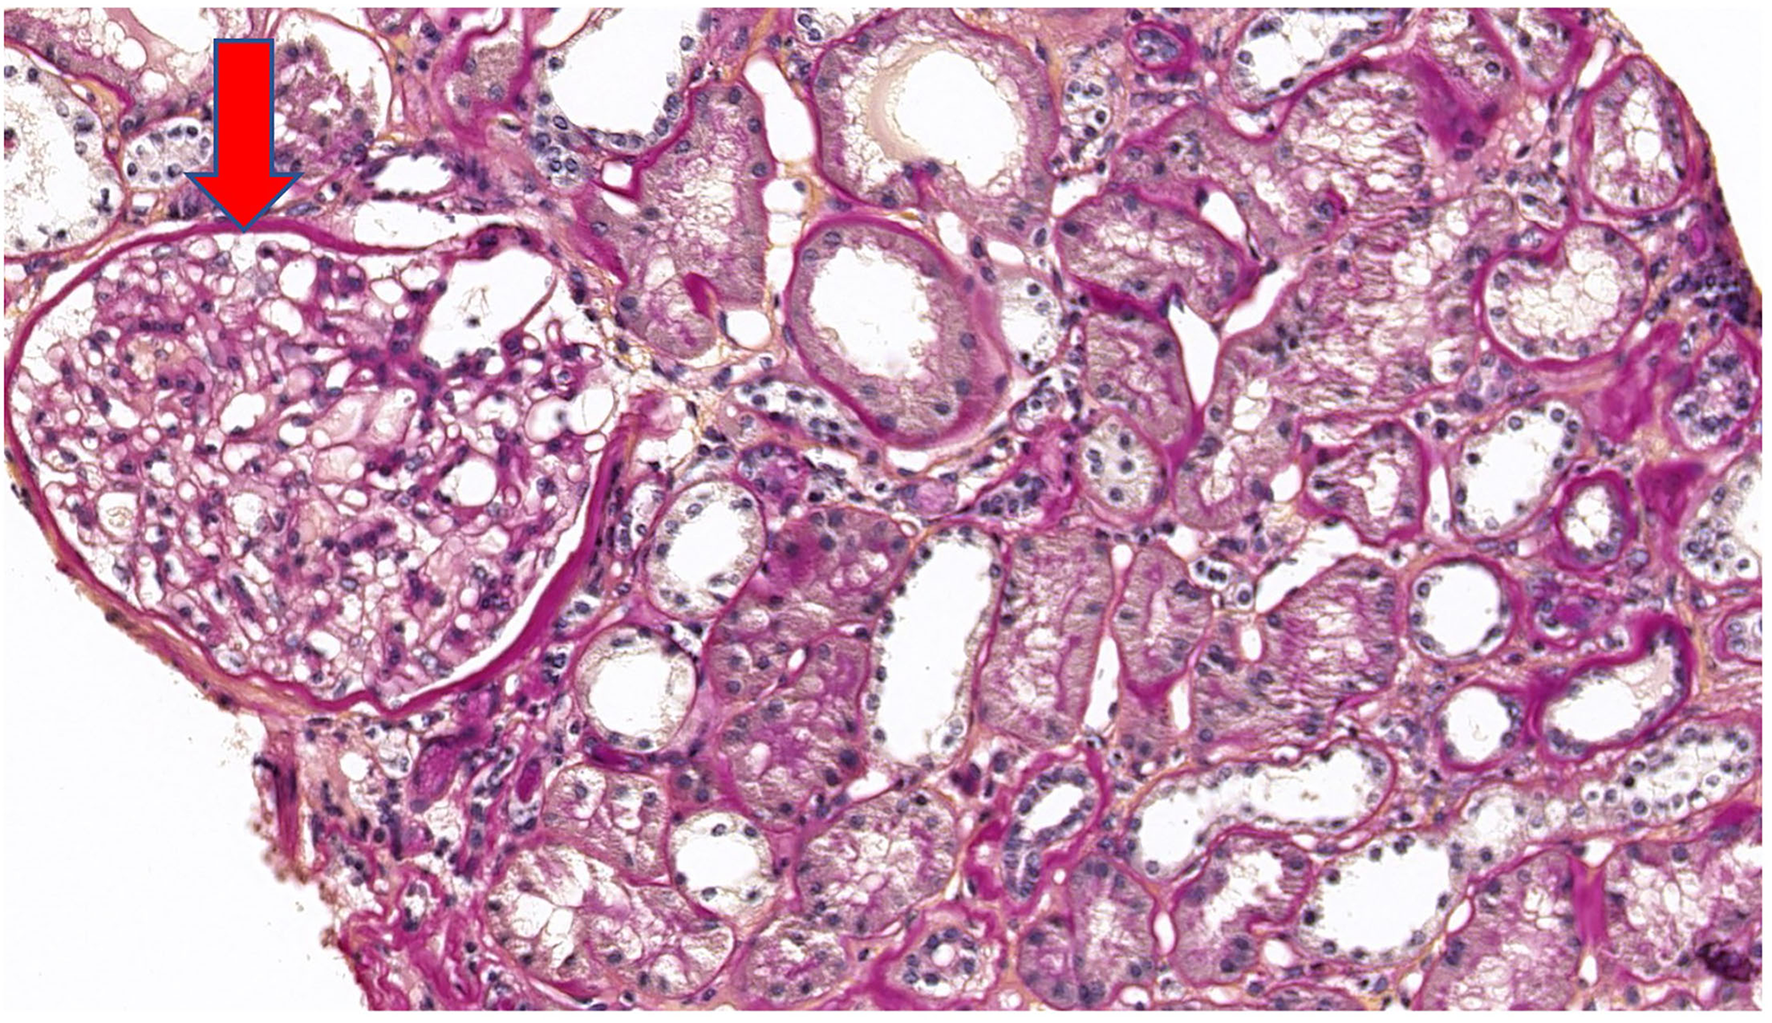

Five years after diagnosis, a serum creatinine of 2.79 mg/dL justified a kidney biopsy. Light microscopy (Figure 3) showed six glomeruli, five of which were within normal limits while one presented advanced sclerosis. Lesions of mild interstitial fibrosis and tubular atrophy were described. Arteries showed moderate arteriosclerosis (Figure 4). Immunofluorescence staining and electron microscopy have not been performed because frozen and glutaraldehyde fixed tissue were not available. An episode of pre-eclampsia occurred during the same year, leading to delivery at 26 weeks and post-natal death of twins.

Figure 3

Periodic acid Schiff (PAS) stain at ×20 magnification on light microscopy showing a normal glomerulus (arrow).